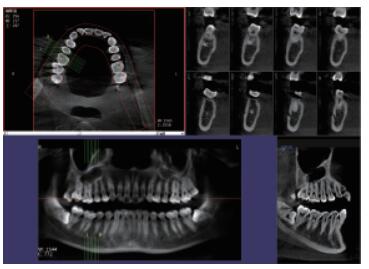

4、口腔CBCT(口腔CT)

CT相對(duì)其他牙片來(lái)講,不管是功能還是設(shè)備上都是比較高級(jí)的,醫(yī)生可在電腦上進(jìn)行模擬種植360°的旋轉(zhuǎn)查看口腔狀況,不遺漏任何一個(gè)角落,主要用于根管治療前、阻生牙、根尖囊腫、種植牙、正畸等。